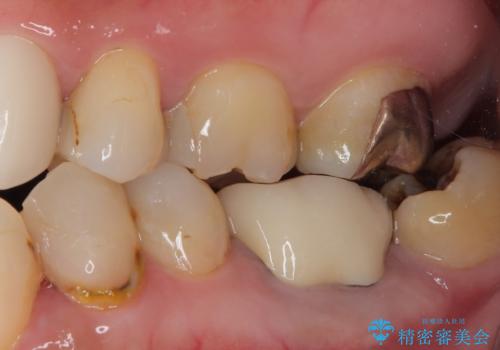

下顎大臼歯の再根管治療とオールセラミッククラウンによる補綴治療

根管治療後は、ファイバーコアによる土台と、オールセラミッククラウンによる補綴治療を行いました。

なお、最後方臼歯が手前に傾いていることで汚れがたまりやすい形態を改善するための矯正治療も提案しましたが、希望されなかったためそのまま補綴治療を行っています。

根管治療後、噛んだ時の違和感は消失しました。

歯ブラシだけでは清掃しにくいところは、フロスや歯間ブラシ等の補助的清掃器具が有効です。